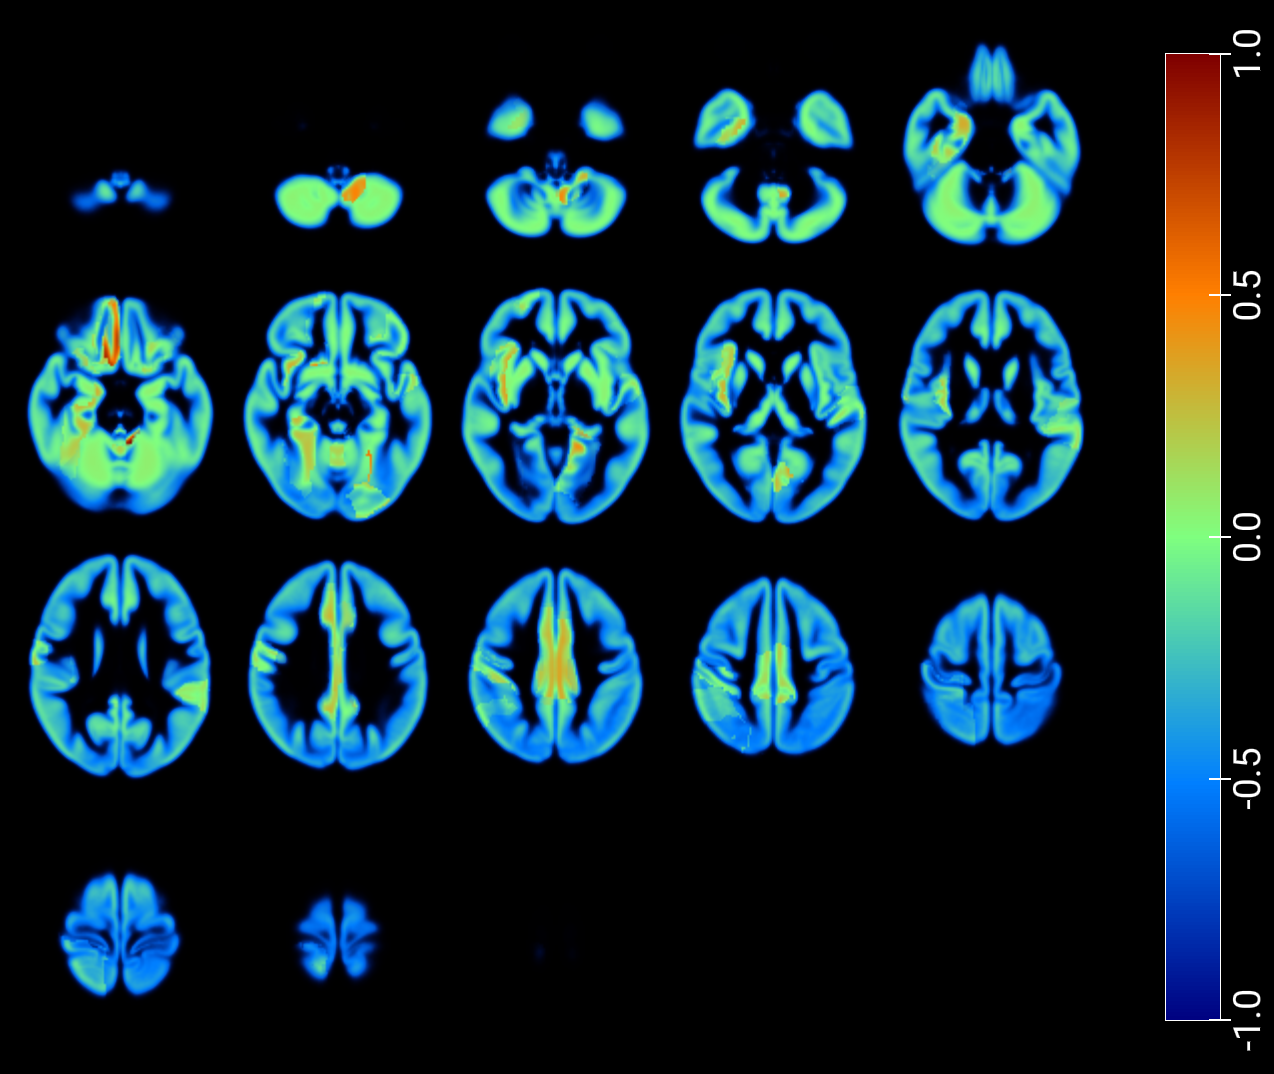

As a critical baseline, we report classification results based on latent features in [2] and provide visualizations of the maximum Pearson correlation values between latent-space activations -projected onto low-dimensional spaces- and region-wise average intensities, stratified by class, and fused with GM MRI (figures 7 and 8). These results explore the correspondence between network activations and anatomical signal distributions and whether it differs across clinical conditions (e.g., AD vs. NOR). This offers a transparent alternative to assess model interpretability and underscores the need for more rigorous and nuanced validation practices in the field.

An inspection of the groups and regions with the highest correlations reveals overlapping areas across clinically relevant comparisons in image reconstruction, as summarized for the t-SNE–based projections in Table 2. These regions correspond closely to those identified through the SHAP analysis presented in the following section (Table 3).

| NOR, AD | NOR, MCI | Cingulum_Mid_R, Frontal_Mid_L, Insula_R |

| NOR, MCI, MCIc, AD | Cerebelum_Crus2_R, Frontal_Mid_L, Insula_R | |

| NOR, MCIc | Frontal_Mid_L, Frontal_Mid_R, Frontal_Sup_L | |

| NOR, MCI | NOR, MCI, MCIc, AD | Frontal_Inf_Oper_L, Frontal_Mid_L, |

| Insula_R, Temporal_Mid_L | ||

| NOR, MCIc | Frontal_Mid_L, Temporal_Mid_L | |

| NOR, MCI, MCIc, AD | NOR, MCIc | Frontal_Mid_L, Heschl_L, Temporal_Mid_L |